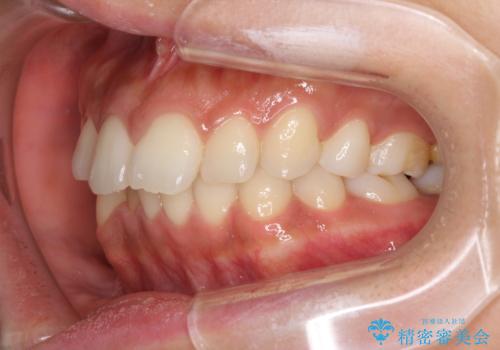

抜歯矯正の後戻り インビザラインによる再矯正治療

- 以前矯正治療をされていましたが、後戻りが起きたことを気にして来院された患者様です。

全顎的に認められた叢生を改善するため、インビザラインにて治療を行うこととしました。

前歯の叢生の改善を目的として、IPR(歯と歯の間を削る)と歯列全体の後方移動によって歯並びを整えることとしました。

毎日22時間の装着時間を守ってくださいましたが、ハイペースにマウスピースを交換することなく、慎重に治療を進めてくださったので、治療期間はやや長くなりました。

臼歯部も含め、叢生が綺麗に改善され、患者様には大変満足していただきました。